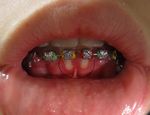

البثور حول الفم

Herpetic gingivostomatitis Herpetic gingivostomatitis is often the initial presentation during the first herpes infection. It is of greater severity than herpes labialis which is often the subsequent presentations. Around 90% of the U.S. population is affected with this disease.[1]

Herpesgingiva.JPG